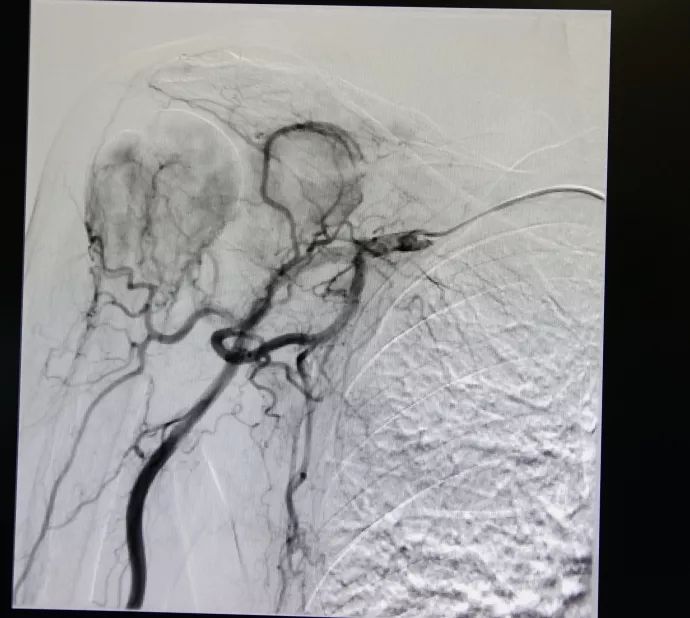

李先生于2018年在复大肿瘤医院首先做了直肠肿块穿刺活检术,病理示:(直肠)低分化腺癌。于是他复查CT示“多发骨转移瘤较前增多、范围较前增大,胸7椎管较前稍变窄;双侧髂血管旁、腹股沟区及直肠周围脂肪间隙淋巴结较前增大”。复大肿瘤医院疼痛科副主任杨清峰及其他专家联合诊治后,因为他曾经在别的医院有术后感染的情况,故决定先给予他介入治疗消除他的疼痛感,因为介入治疗具有很高的安全性和很低的风险性,可以降低术后感染的情况发生。

治疗前 治疗后

“患者已是直肠腺癌T4N2M1 Ⅳ期,姑息治疗可以有效缓解他的疼痛” 介入治疗的主治医生杨清峰表示,“姑息治疗也可以有所作为,不仅能够改善病人的生存质量,还有助于延长生存时间。个别情况下,甚至能创造生命的奇迹”。

2019年经CT复查显示李先生部分病灶缩小,患者四肢疼痛感明显缓解,睡眠良好,生活可以自理了,“真是很神奇的,感觉就是睡了一觉,醒来后发现胳膊与腿都能自如活动了,我之前只能躺着,抬一下胳膊都会很痛”,经过介入治疗后李先生这样说。